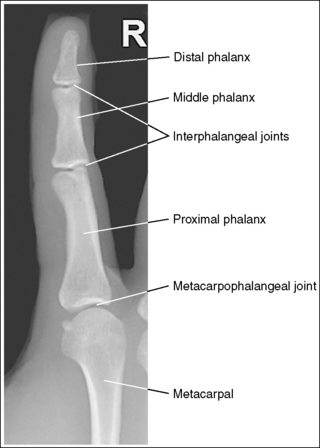

See Figure 4-10 and Box 4-4.

The digit of interest is in a lateral projection. The anterior aspect of the middle and proximal phalanges demonstrates midshaft concavity, and the posterior aspects of the phalanges show slight convexity.

• A lateral finger projection is accomplished by rotating the affected finger 90 degrees from the PA projection (Figure 4-11). Whether the hand is rotated internally or externally to obtain this goal depends on which direction will bring the finger closer to the IR. Typically, when the second and third fingers are imaged, the hand is rotated internally and, when the fourth and fifth fingers are imaged, the hand is rotated externally.

• Distinguishing lateral projection from rotated projection. To understand the difference between a truly lateral digit projection and a lateral projection that is rotated, study a finger skeleton in lateral and PA and AP oblique projections. Note how the midshaft concavity of the middle and proximal phalanges varies as the digit is rotated. In a lateral projection, the anterior aspect of these phalanges is concave, but the posterior aspect demonstrates slight convexity. In PA and AP oblique projections, both sides of the middle and proximal phalangeal midshafts demonstrate concavity, but the side toward which the anterior surface is rotated demonstrates a greater degree of concavity than the side toward which the posterior surface is rotated. The soft tissue width at either side of the phalanx also changes in the lateral and PA and AP oblique projections. More soft tissue is present on the side of the phalanges toward which the anterior surface is rotated (see Image 7).

The IP joints are visible as open spaces, and the phalanges are not foreshortened.

• The IP joints are open, and the phalanges are demonstrated without foreshortening as long as the finger was positioned parallel with the IR and the central ray was perpendicular to and centered with the PIP joint.

The PIP joint is at the center of the exposure field. The distal, middle, and proximal phalanges and the metacarpal head of the affected digit are included within the collimated field.

• Center a perpendicular central ray to the PIP joint to place it in the center of the image. Open the longitudinal collimation to include the distal phalanx and the metacarpal head. Transversely collimate to within 0.5 inch (1.25 cm) of the finger skin line.